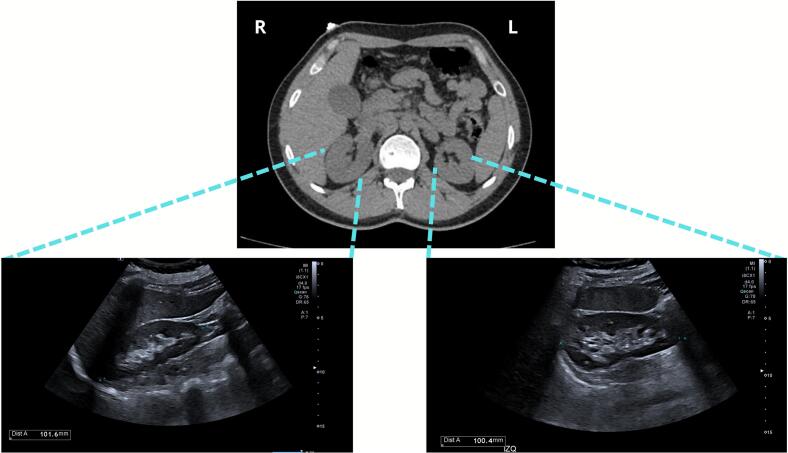

Abdominal ultrasound demonstrated normal hepatobiliary structures (liver, gallbladder, bile ducts), pancreas, spleen, and kidneys (10 cm longitudinal diameter, preserved parenchyma) (Fig. 3), without evidence of stones, masses, pelvicalyceal dilation, or retroperitoneal lymphadenopathy. The abdominal aorta was unremarkable in caliber.